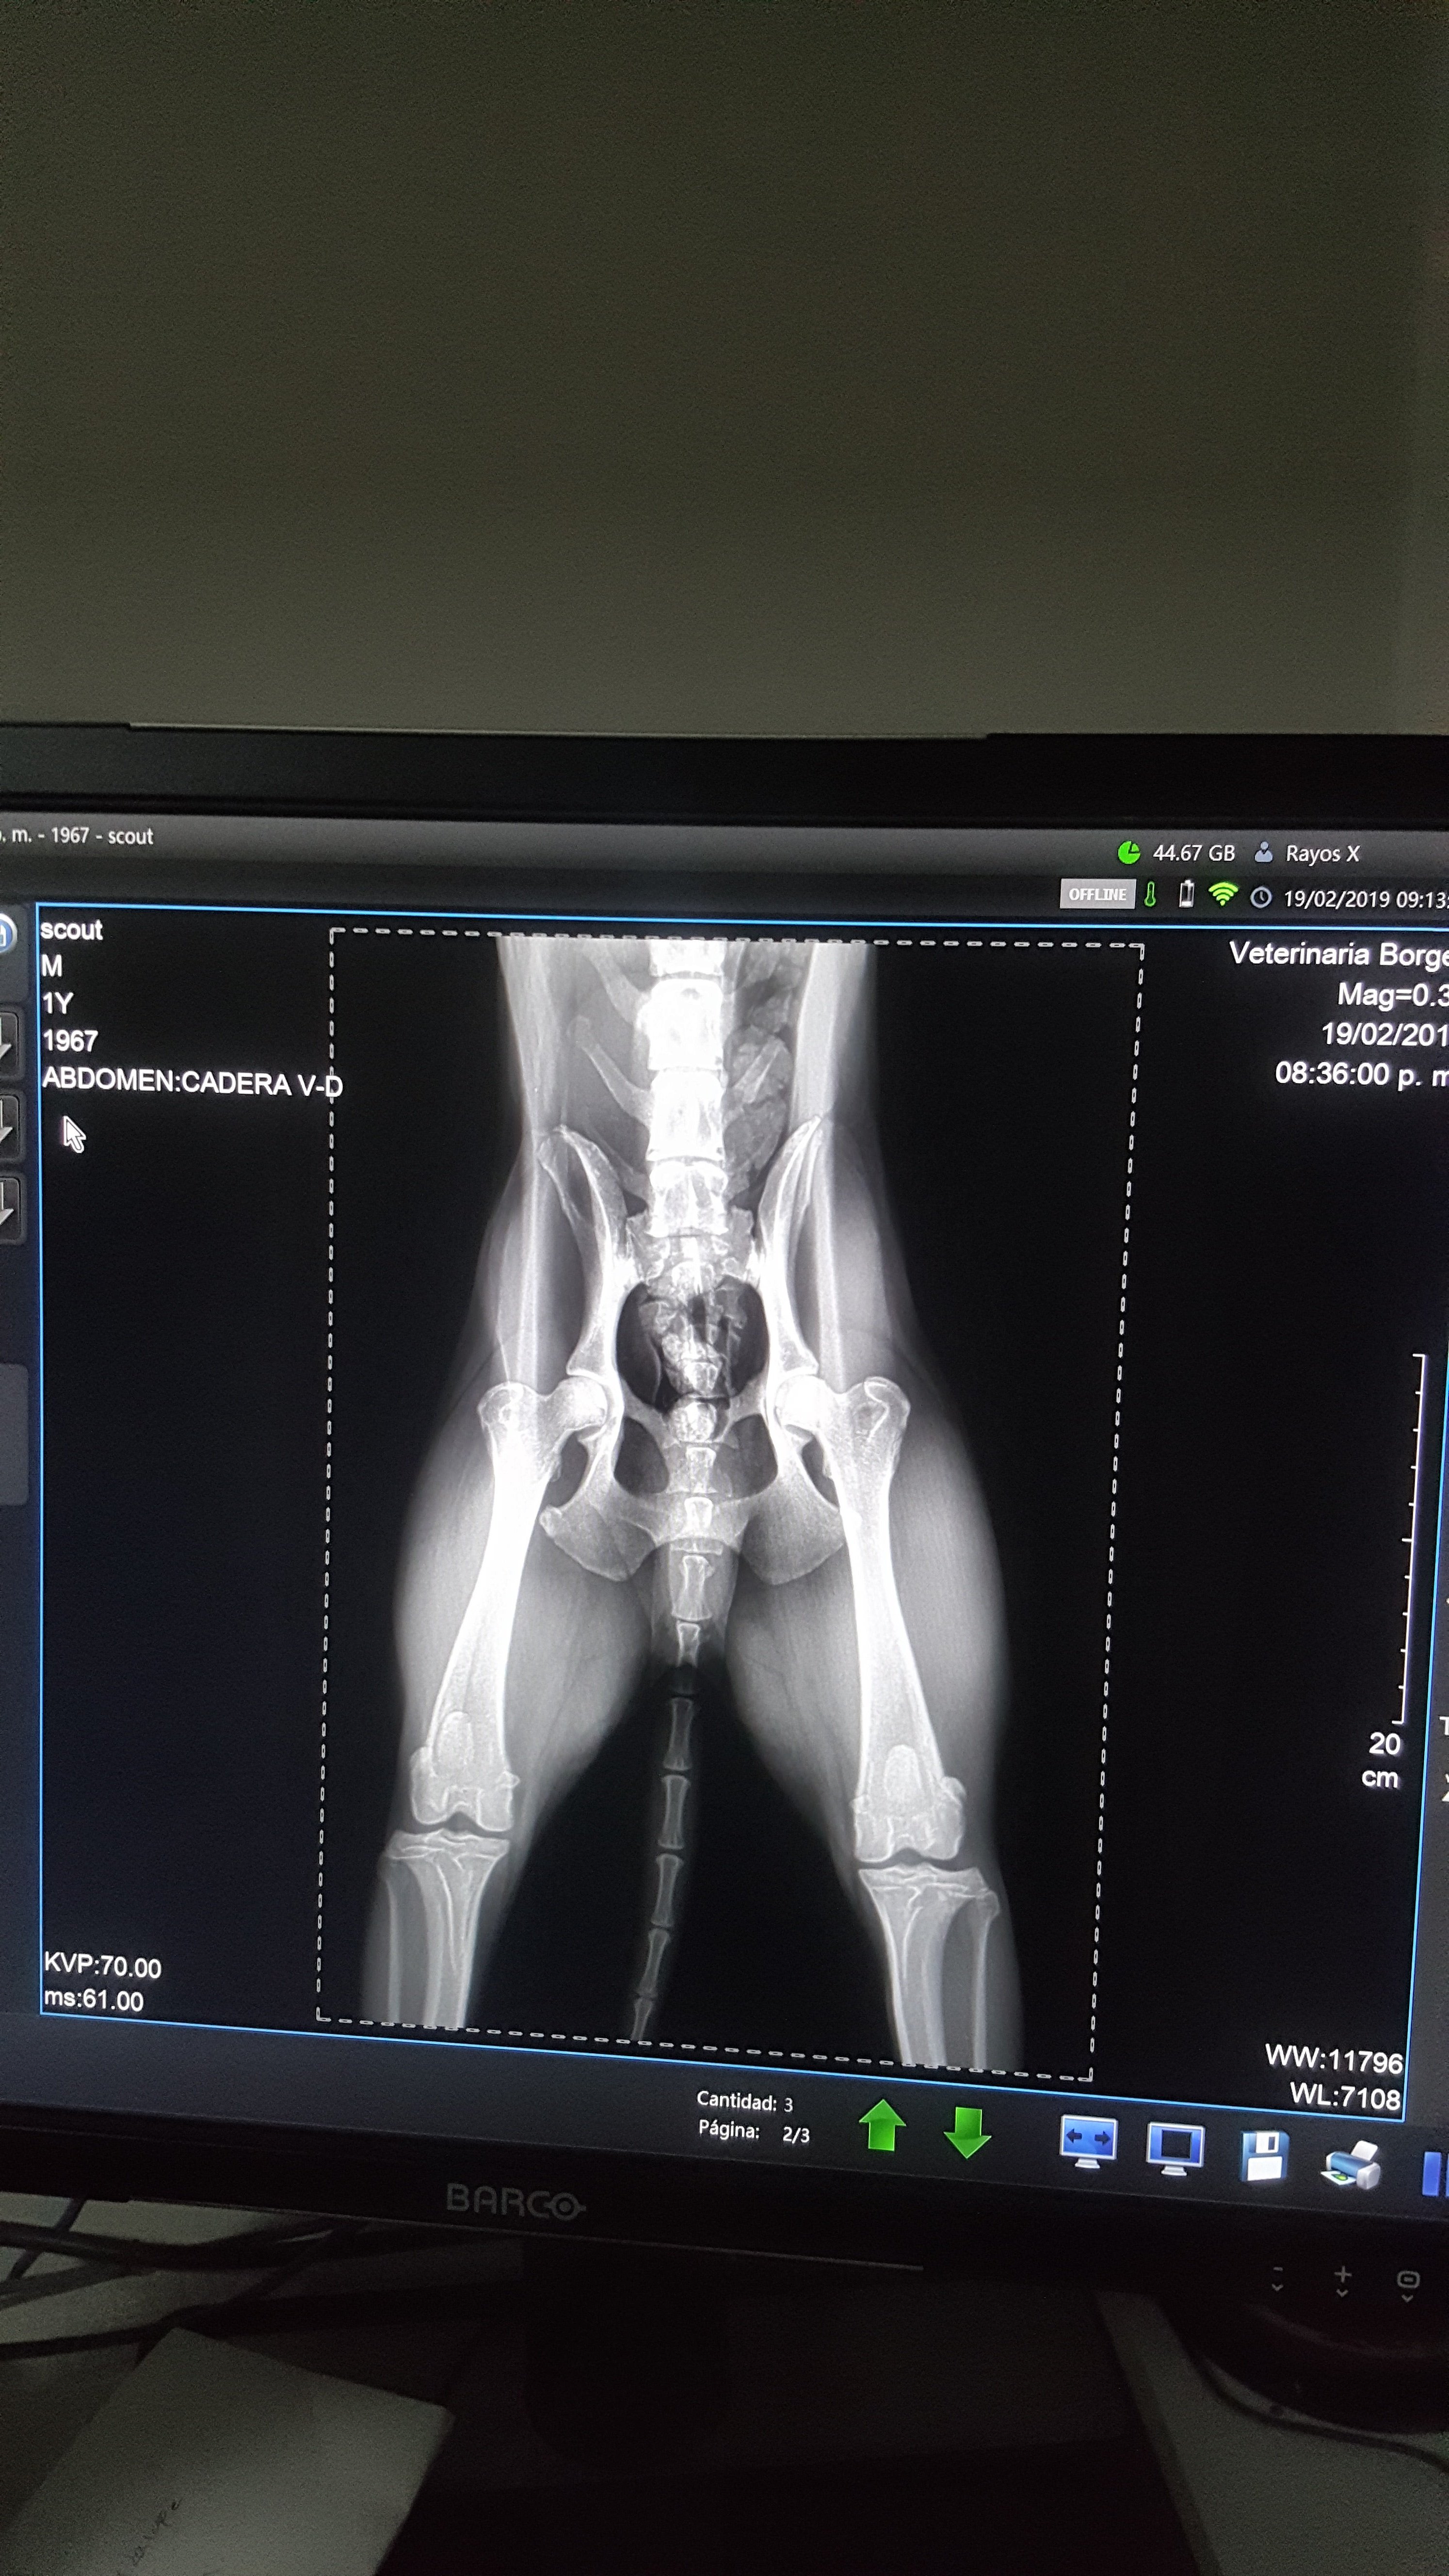

We had to take Scout to the vet this last week because he began to limping due to an abscess on his foot. He had to get it cut and drain. While we were there, we had X-rays done on his hips to determine if he had hip dysplasia, but as it turns out he does not. His hips are actually in good shape which is unusual for his breed and given that he’s over 13 years old and lived an active life.